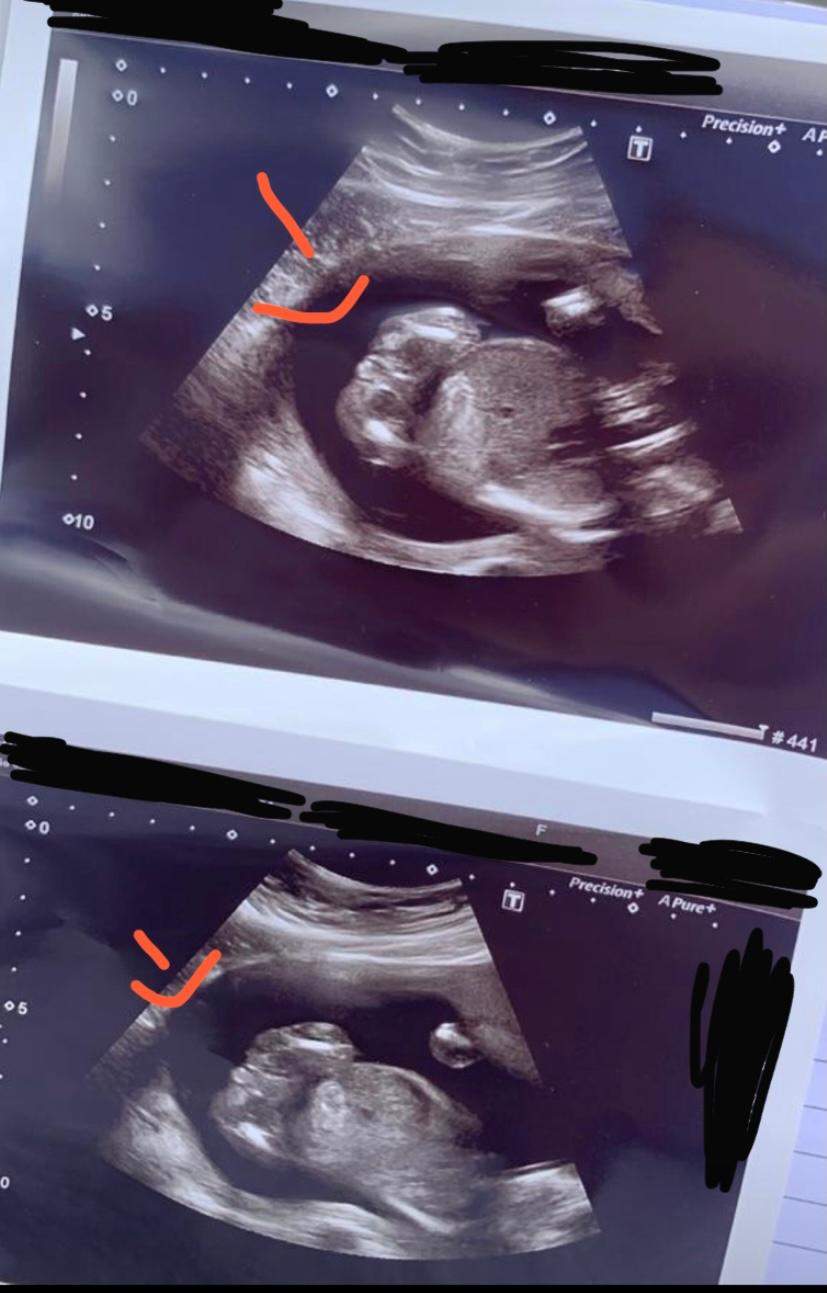

In einer neueren Studie konnten Sonographie-Experten das Geschlecht in Schwangerschaftswoche 12 nur bei 46 Prozent aller Babys richtig bestimmen. In der 20 SSW bestätig anhand des Bildes siehe unten Mein kleiner ist nun 4 wochen alt.